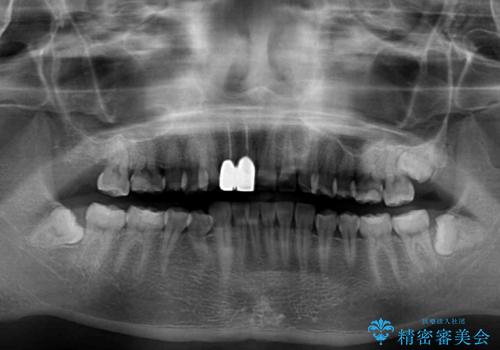

クラウンの状態は、根管治療の状態も含めて決して良い状態とは言えず、矯正治療後の根管治療と補綴治療の再治療を前提として、インビザラインによる矯正治療を行うこととしました。

矯正治療中に前歯2本のクラウンは外れてしまい、途中仮歯に替える必要があったので期間は掛かりましたが、歯列も整い、負担のかからない咬み合わせを達成することができました。